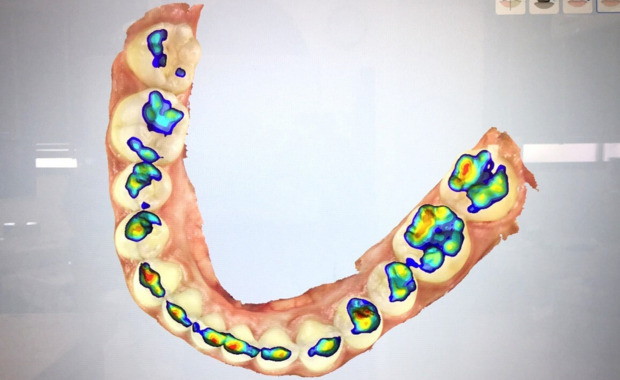

口腔内スキャナー

歯科における口腔内スキャナーで、3Dデジタルモデルを作成するための医療機器です。初期の虫歯や、歯石を発見し噛み合わせの強さを可視化できます。精密な診断と治療計画を立てるために使用しますので、当院では初診時、全ての患者様にご案内いたします。また、スキャン後はモニターに映し出し、360度あらゆる角度から歯や歯茎の状態を確認できるので、患者様と一緒にご自身の歯の状態をチェックできます。また、詰め物や被せ物の作成時の型取りについても、こちらの機械を使用します。従来の型取り材を使用するよりも、2〜3分程度という非常に短時間で撮影が完了します。より精密で、負担も少なく快適に型取りを行えます。